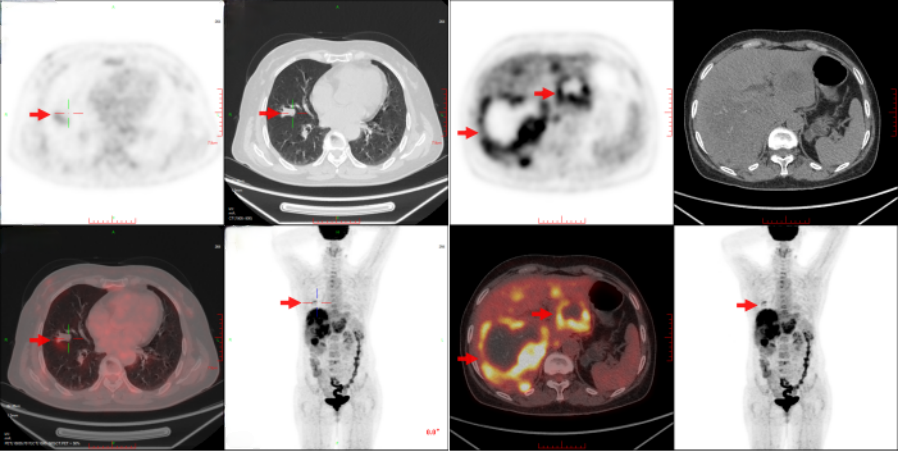

6)上腹部增强CT检查(2023/03/09)

右肺中叶实性结节,较前变化不大;左肺多个结节,部分较前新发,余较前变化不大;肝内多发结节及肿块,部分较前增大,考虑肝恶性肿瘤,肝左叶实质及病变内增碘油沉积,较前减少(图3)。

图3 患者上腹部增强CT图像

根据CSCO神经内分泌肿瘤诊疗指南(2022年版),对于外科手术无法达到根治的患者,建议系统性全身治疗,从而抑制肿瘤增殖、控制激素相关症状。同时,可结合手术、TAE 或射频消融术等局部治疗以降低肿瘤负荷。可用于全身治疗的药物有生长抑素类似物(如奥曲肽兰瑞肽)、分子靶向药物(如索凡替尼依维莫司)、肽受体介导的放射性核素治疗(PRRT)、细胞毒性化疗、免疫治疗(尚处于临床探索阶段)等。经肿瘤多学科协作(MDT)讨论后建议全身靶向药物联合局部介入抗肿瘤治疗,患者自行口服索凡替尼靶向抗肿瘤治疗,偶有腰背部疼痛不适,可耐受;2023年1月31日行第一次肝动脉化疗栓塞术+肝动脉置管化疗术,术后恢复可。2023年3月9日复查上腹部增强CT示肝内多发结节及肿块,部分较前增大,排除禁忌后于2023年3月15日再次行肝动脉化疗栓塞术,手术顺利,术后予以保肝、补液、护胃等对症支持治疗。

2 个疗程后复查CT:肝内多发结节及肿块,部分较前增大,考虑肝恶性肿瘤,肝左叶实质及病变内增碘油沉积,较前减少;右肺中叶实性结节,性质待定,较前变化不大。根据RECIST 1.1疗效评估:疾病稳定(SD)。